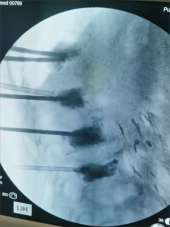

7. 复杂脊柱骨折内固定技术

随着区域内社会经济开发,复杂严重脊柱脊髓损伤病例增加,如何良好的手术治疗解除脊髓压迫、重建脊柱稳定性,使患者创伤最小、收益最大是促进患者康复至关重要的一环。我院已熟练开展各类脊柱损伤修复重建技术,每年完成复杂脊柱骨折手术处于区域领先水平。